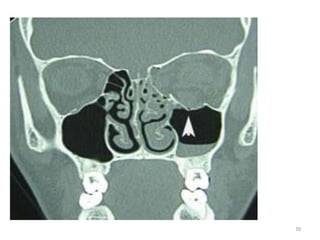

Image shows depressed fragment of the left orbital floor (arrow)

and an air-fluid level in the left maxillary sinus